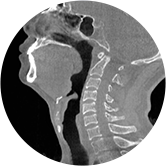

气道

颈椎

气道三维影像重建